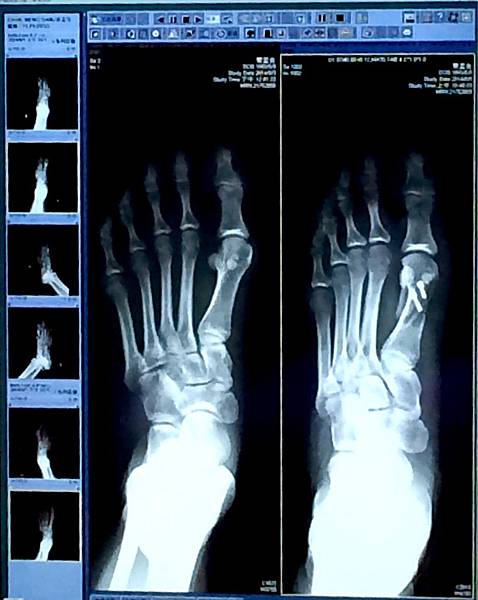

看到術後隔天拍的X光片最開心~~~

因為骨頭變直好多